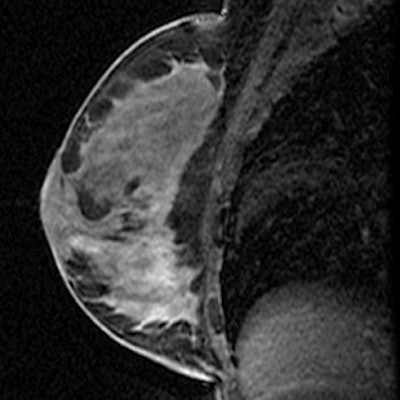

| Sagittal T1-weighted contrast-enhanced image after biopsy and clip placement shows signal void from marker in retroareolar region (arrow) in this image obtained during same sequence but just lateral to slice seen in top image. Histologic analysis of material obtained at MRI vacuum-assisted biopsy yielded benign breast parenchyma with dense stromal fibrosis, discordant with imaging. |